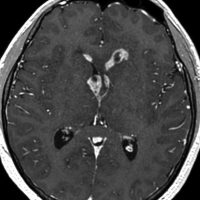

ガドリニウム増強では,前頭葉腫瘍というより,側脳室壁にベトベトくっついているような腫瘍です。germinoma特有のsubependymal infiltration像を示します。

生検後2ヶ月,セカンドオピニオンのために受診された時の画像です。腫瘍が縮小傾向にあります。入院中に行われた何度かのCT被曝の影響で,germinomaの退縮が生じたのだと判断しました。